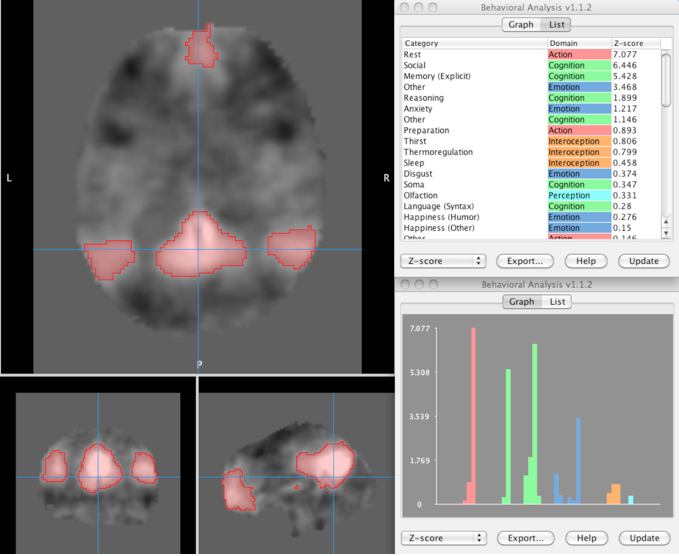

Description: The Behavior Analysis plugin performs regional behavior analysis based on a user selected brain region of interest (ROI). The image where the ROI is defined must be in the Talairach brain space before processing. You should verify that the origin is correctly positioned (press 'o' key in Mango), since analysis is coordinate based. Talairach spatial normalization can be done using Mango's SN plugin for anatomical images. If your image was aligned using the MNI brain template you can use the MNI-to-Tal transform, which is an option in the transform menu (Mango v2.6 and later).

Results of behavior analysis are presented for BrainMap's five Behavioral Domains (Action, Cognition, Emotion, Interoception, and Perception) and sixty sub-domains (figure). Only z-scores >=3.0 are considered significant (p<=0.05 with Bonferroni correction for multiple comparisons). A behavior profile chart and z-score ranked table (figure) are provided to assist with interpretation.

The figure is an example of using behavior analysis with resting state ICA images. Data in the figure is for the ICA representing the default mode network (Smith et al., PNAS 2009). The red ROI was made using a threshold at z=3.

Four reasonable behavior sub-domains were statistically significant for this example: